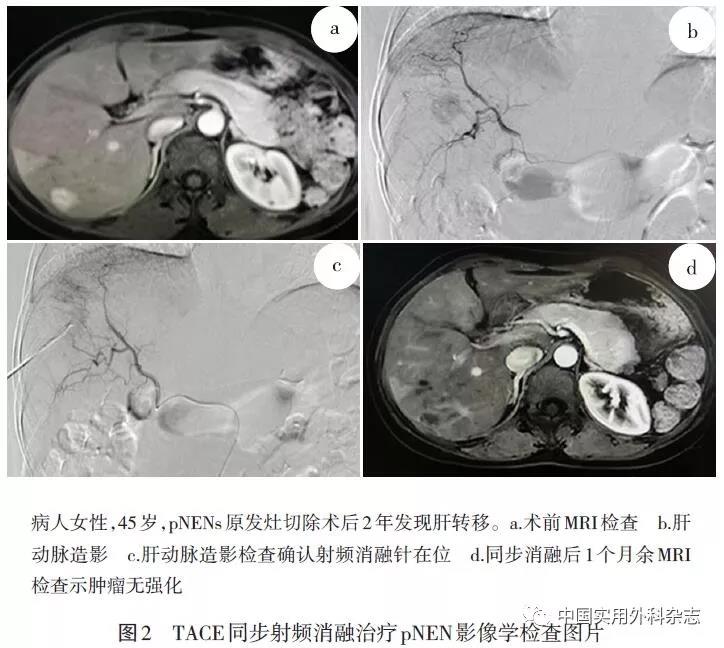

1.2.3 TACE同步经皮肝肿瘤热消融术 术前准备同TACE,通过肝总动脉和肠系膜上动脉进行动脉血管造影。依据术中肿瘤染色情况,超选择至肿瘤供血血管。结合术前影像及术中DSA、超声检查结果,制定穿刺路径,局麻,消融针进入病灶消融,消融结束后再次造影,明确病灶坏死情况以及是否有出血或动脉门静脉瘘的发生,如发现残留血管染色,根据残留血管染色位置选择消融治疗或TACE治疗(图2)。

2.2 疗效及并发症 45例病人共行186次TACE、15次射频消融、10次微波消融,其中14次为TACE同步热消融治疗,共计211次治疗,平均治疗次数为4.7次。参照mRECIST标准,CR、PR、SD和PD分别为19、138、40和14次,其中热消融治疗评估为CR、PR、SD和PD分别为13、11、0和1次。 TACE的总有效率为71.5%,热消融治疗的总有效率为96.2%(单消融 91.7%、同步消融 100%)。见表2。